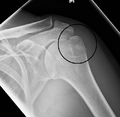

A fracture of the greater tubercle of the humerus

Fracture of the greater tubercle of the humerus

Fracture of the proximal humerus with involvement of the greater tubercle